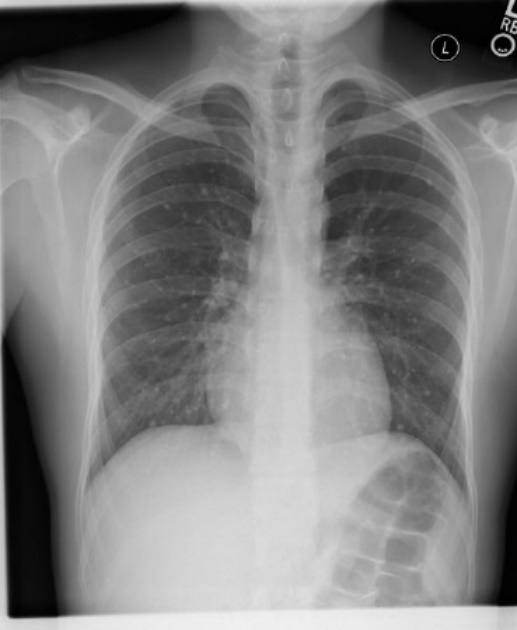

Сау өкпе

Пневмониялы өкпе

Бұл ауруларды рентген немесе компьютерлік томография (КТ) суреттері арқылы анықтауға болады. Бірақ кейде дәрігерлердің жүктемесі көп болғандықтан, ауруды байқамай қалу қаупі бар.